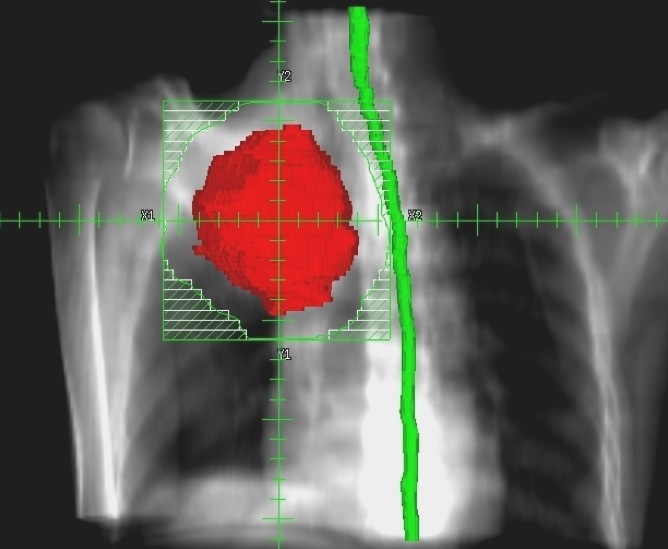

まず申し上げたいのは、最近の放射線治療は「がん」治療のかなでも副作用の少ない治療法とされています。それには多くの技術革新があっての結果ですが、一般にピンスポイント照射とも呼ばれている高精度な三次元治療計画が最も重要な役割を果たしています。それは副作用のでやすい臓器を避けて病巣に放射線を集中照射する技術です。写真4をご覧ください。

赤い肺癌に放射線照射を行うときに最も注意しなければならないのは緑の脊髄です。画像情報を駆使して、脊髄障害を起こさずに肺癌病巣に照射する方法を事前に十分検討してから、最も良い方法を選んで実際の治療を行うのです。写真5は主に食道に放射線を集中しものですが、ここでは前後にある心臓と脊髄を避けて4方向から照射しています。この方法で癌病巣や脊髄・心臓にどの位の放射線があたるのかを写真6のようなグラフを描いて評価します。したがって、昔のコバルト治療時代の副作用とは比較にならないほど軽く済むことが多くなりました。それでも副作用には個人差があり、特に治療中に発生する早期反応は化学療法でも強まり、ある程度は我慢しなければならない場合もあるでしょう。さらに副作用に対応する腫瘍看護学も進歩しており、日常のケアが行き届くようになっていますので、何か辛いことがあれば医療スタッフに遠慮なく相談したほうがよいでしょう。